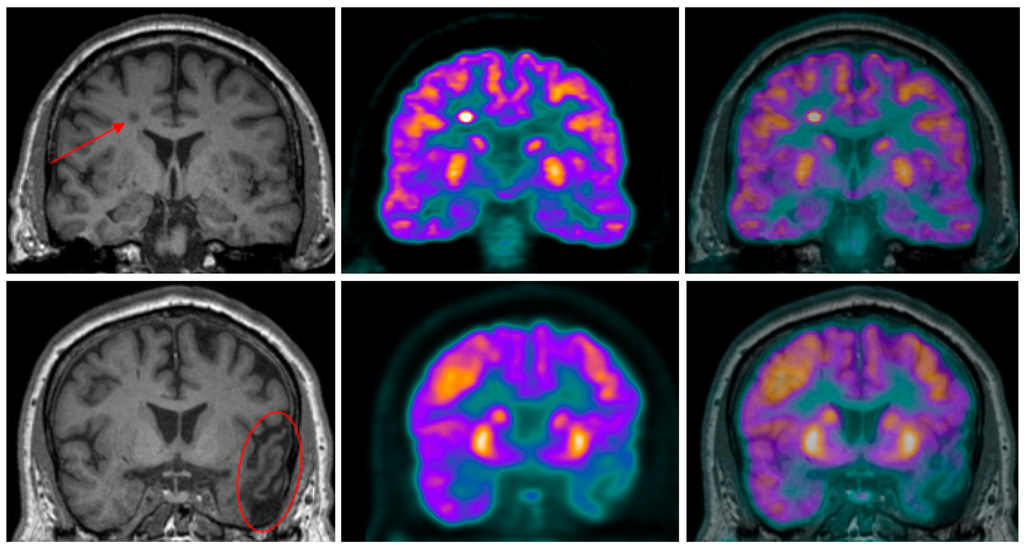

- Garibotto, V.; Heinzer, S.; Vulliemoz, S.; Guignard, R.; Wissmeyer, M.; Seeck, M.; Lovblad, K.O.; Zaidi, H.; Ratib, O.; Vargas, M.I. Clinical applications of hybrid PET/MRI in neuroimaging. Clin. Nucl. Med. 2013, 38, e13–e18. [Google Scholar] [CrossRef] [PubMed]

- Catana, C.; Drzezga, A.; Heiss, W.D.; Rosen, B.R. PET/MRI for neurologic applications. J. Nucl. Med. 2012, 53, 1916–1925. [Google Scholar] [CrossRef] [PubMed]

- Schwenzer, N.F.; Stegger, L.; Bisdas, S.; Schraml, C.; Kolb, A.; Boss, A.; Muller, M.; Reimold, M.; Ernemann, U.; Claussen, C.D.; et al. Simultaneous PET/MR imaging in a human brain PET/MR system in 50 patients—Current state of image quality. Eur. J. Radiol. 2012, 81, 3472–3478. [Google Scholar] [CrossRef] [PubMed]